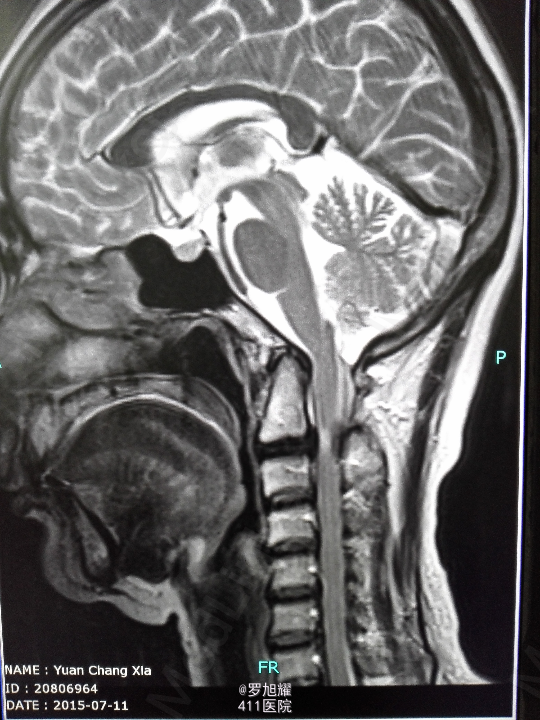

右侧躯体麻木1年,右上肢及下肢麻木2月余。 查体:颈椎活动受限,右上肢肘关节以远痛温觉减退,右侧胸4平面以下痛温觉及触觉减退,四肢肌力尚可,右侧霍夫曼征阳性,右侧上下肢所有腱反射亢进。 颈椎X线示:颈2椎板棘突缺如,颈3棘突肥大增高。 颈椎CT示:颈2椎板棘突缺如,颈3棘突肥大增高,颈2/3椎间盘突出,左侧颈2残留部分椎板进入椎管。枢椎齿突增生,寰枢关节退变。 颈椎MRI示:颈2/3椎间盘突出,左侧颈2椎板进入椎管,颈髓受压变性。

查体:颈椎活动受限,右上肢肘关节以远痛温觉减退,右侧胸4平面以下痛温觉及触觉减退,四肢肌力尚可,右侧霍夫曼征阳性,右侧上下肢所有腱反射亢进。 颈椎X线示:颈2椎板棘突缺如,颈3棘突肥大增高。 颈椎CT示:颈2椎板棘突缺如,颈3棘突肥大增高,颈2/3椎间盘突出,左侧颈2残留部分椎板进入椎管。枢椎齿突增生,寰枢关节退变。 颈椎MRI示:颈2/3椎间盘突出,左侧颈2椎板进入椎管,颈髓受压变性。

诊断为:颈椎先天畸形、颈2/3椎间盘突出伴不全瘫。 因寰枢关节退变,颈椎活动已部分受限,而且枢椎椎板棘突缺如,稳定性差,决定后路减压枕颈融合。

因寰枢关节退变,颈椎活动已部分受限,而且枢椎椎板棘突缺如,稳定性差,枕颈融合虽然造成颈部活动受限,但是稳定性好,避免脊髓再次损伤。本例手术后半月上肢麻木明显改善,躯干和下肢麻木尚待恢复。